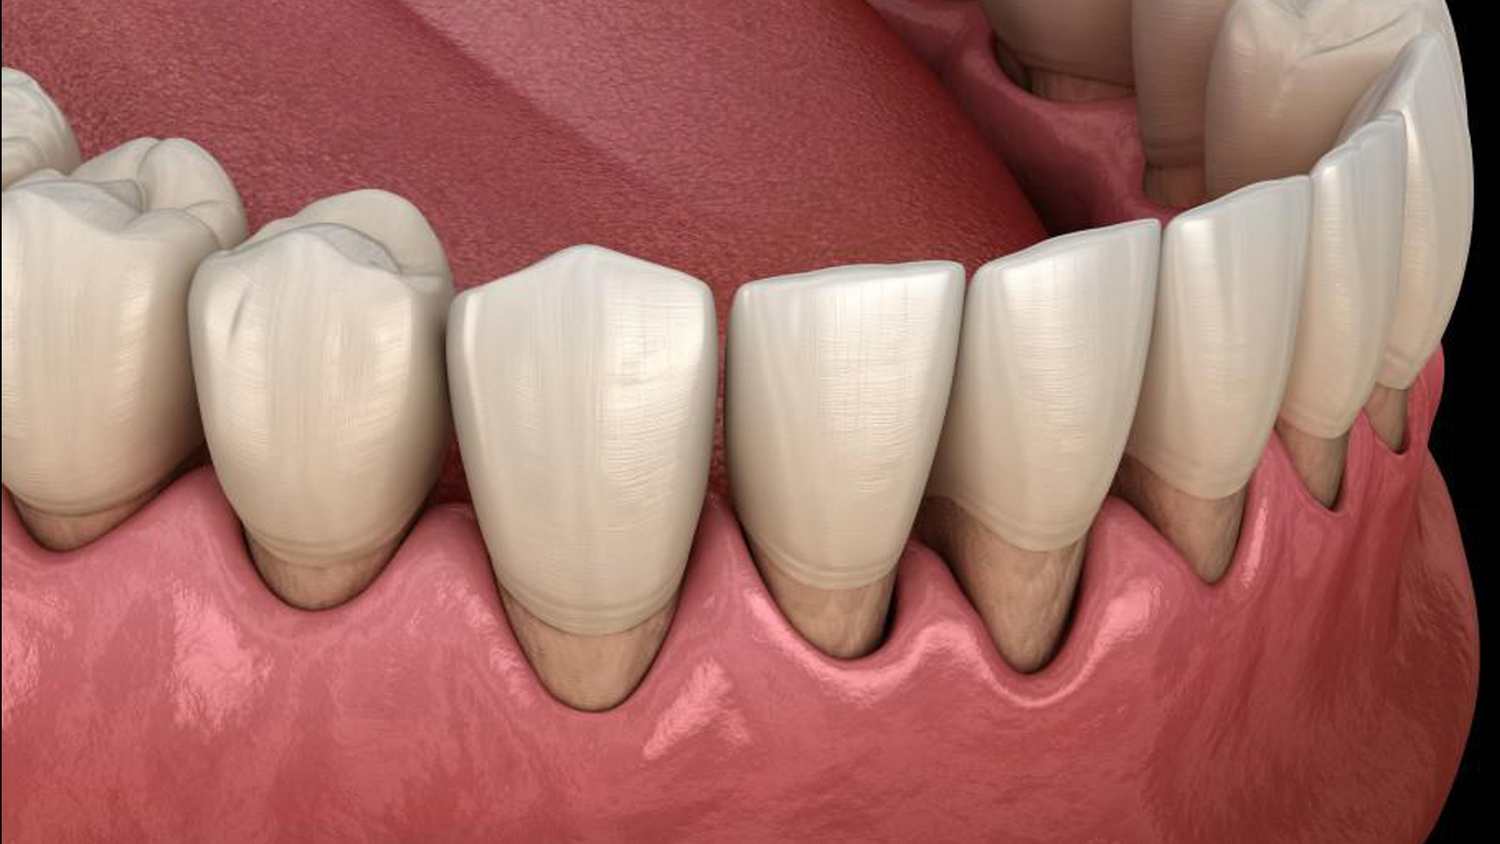

Dişeti Çekilmeleri

Diş eti rahatsızlığı, dişlerimizde sürekli oluşan yapışkan bir bakteri filmi olan plaktan kaynaklanır.

Devamını Oku